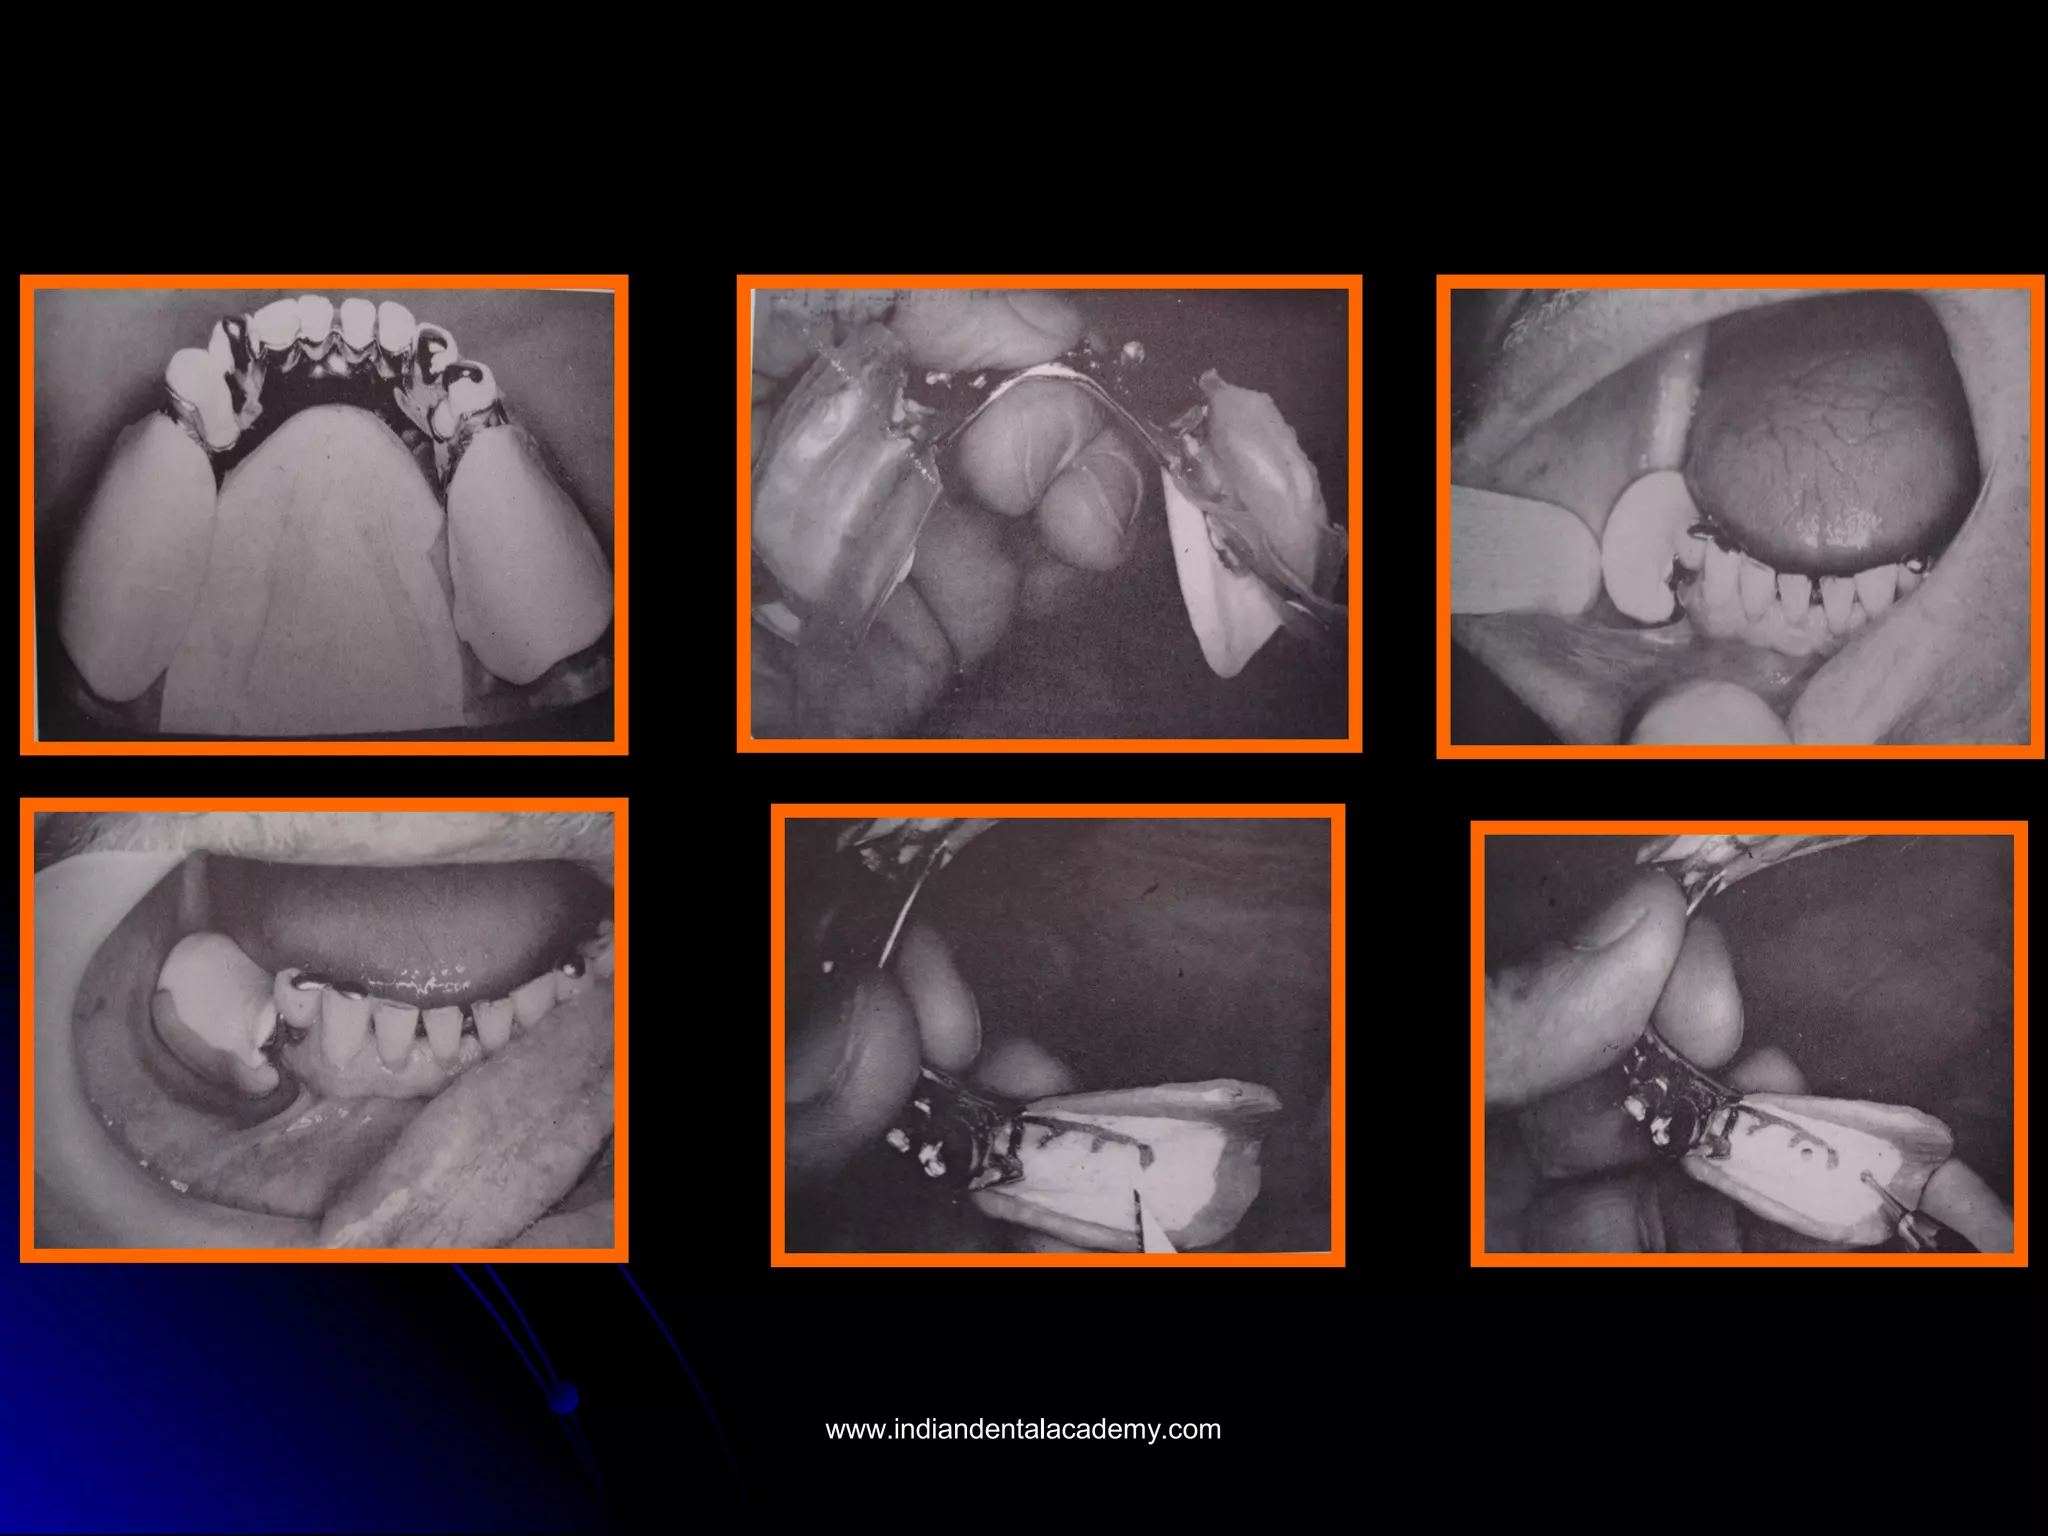

Hindels and other developed irreversibleHindels and other developed irreversible

hydrocolloid trays for the second impression thathydrocolloid trays for the second impression that

were provided with holes so that finger pressurewere provided with holes so that finger pressure

could be applied through the tray as thecould be applied through the tray as the

hydrocolloid impression was made.hydrocolloid impression was made.

www.indiandentalacademy.comwww.indiandentalacademy.com

The main change that Hindels introducedThe main change that Hindels introduced

to McLean ‘s original technique was thatto McLean ‘s original technique was that

the impression of the edentulous ridgethe impression of the edentulous ridge

was not made under pressure but was anwas not made under pressure but was an

anatomic impression of the ridge at restanatomic impression of the ridge at rest

made with a free flowing zinc oxidemade with a free flowing zinc oxide

eugenol paste.eugenol paste.

As the hydrocolloid second impressionAs the hydrocolloid second impression

was being made, however, finger pressurewas being made, however, finger pressure

was applied through the holes in the traywas applied through the holes in the tray

to the anatomic impression. The pressureto the anatomic impression. The pressure

had to be maintained until the alginatehad to be maintained until the alginate

was completely set. The two were relatedwas completely set. The two were related

to each other, however, as if masticatingto each other, however, as if masticating

forces were taking place on the dentureforces were taking place on the denture

base.base.